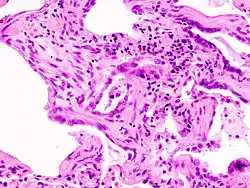

W badaniu rentgenowskim klatki piersiowej stwierdza się zacienienia siateczkowate zlokalizowane u podstawy płuc, zmniejszenie objętości płuc. W badaniu tomokomputerowym widoczne są zacienienia siateczkowate, obraz „plastra miodu” (obszary drobnych torbieli[3]), ogniskowe, słabo widoczne zmiany o charakterze „mlecznego szkła” (nieznaczne zacienienie obszaru płuc z widocznym rysunkiem naczyń krwionośnych[3]) oraz rozstrzenie oskrzeli. Zmiany zlokalizowane są na obwodzie płuc. W gazometrii można stwierdzić hipoksemię. W badaniach czynnościowych płuc (np. spirometria) stwierdza się cechy restrykcji. Obniżona jest zdolność dyfuzyjna gazów w płucach. Nieprawidłowy jest wynik testu sześciominutowego marszu. W diagnostyce wykorzystuje się również badanie histopatologiczne tkanki pobranej w czasie biopsji płuca, w którym obserwuje się zmiany zapalne zlokalizowane śródmiąższowo (obraz tzw. zwykłego śródmiąższowego zapalenia płuc[2][4]).

Badanie histopatologiczne jest konieczne do pewnego rozpoznania choroby (dotyczy to badania histopatologicznego materiału pobranego z płuca podczas biopsji wykonanej od zewnątrz). Idiopatyczne włóknienie płuc można też ewentualnie rozpoznawać na podstawie cech klinicznych choroby, w tym wypadku należy u pacjenta stwierdzić wszystkie 4 kryteria większe i 3 spośród 4 kryteriów mniejszych ustalonych przez Amerykańskie Towarzystwo Klatki Piersiowej oraz Europejskie Towarzystwo Oddechowe[5]: